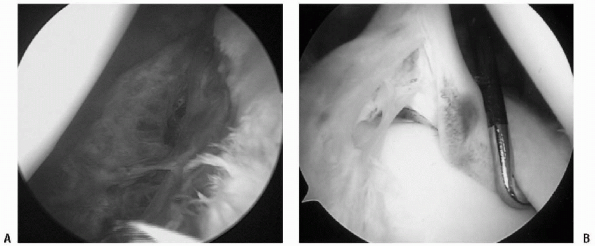

![]() |

Figure 17-3

Arthroscopic view of an anterior labrum periosteal sleeve avulsion lesion. Anterior view of the left shoulder with the lesion being mobilized. |

lesion and an anterior labral ligamentous periosteal sleeve avulsion

lesion (ALPSA) (Fig. 17-3). In both acute and

chronic anterior dislocations, the anterior scapular periosteum does

not rupture as in a Bankart lesion, but the anterior IGHL, labrum, and

the anterior scapular periosteum are stripped and displaced in a

sleeve-type fashion medially on the glenoid neck. This is an important

diagnostic variant to recognize because in a chronic situation, a

cursory inspection of the anterior-inferior quadrant of the glenoid may

not reveal evidence of trauma. However, closer inspection more medially

will show a large, medially displaced scarred labrum on the anterior

portion of the glenoid neck.